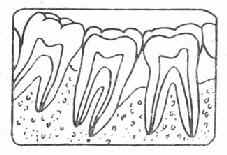

牙周袋形成:由于炎症的扩展,牙周膜被破坏,牙槽骨逐渐吸收,牙龈与牙根分离,使龈沟加深而形成牙周袋。可用探针测牙周袋深度。X线检查时可发现牙槽骨有不同程度的吸收。如图3-7~11.

| 图3-9 牙槽骨Ⅱ吸收 | 图3-10 牙槽骨Ⅲ吸收 |